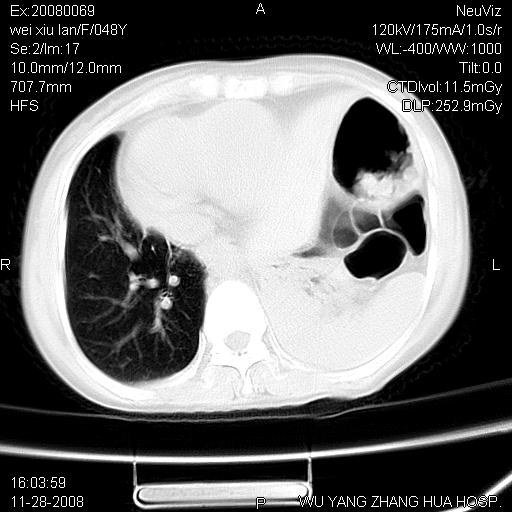

标题: CT16847:女,48岁,咳嗽,发热两日,平常偶有上腹部不适。 [打印本页]

标题: CT16847:女,48岁,咳嗽,发热两日,平常偶有上腹部不适。

能否考虑食管裂孔疝?请老师们多多指教。

这个是左侧膈膨升伴不完全性胃翻转,手术将松弛的左横膈膜折叠缝合即解决问题。

支持左侧膈疝,心脏受压右移.

胃、脾脏及部分肠管明显升高,并压迫心脏移位,

首先考虑:左侧膈疝。

左侧胸腔内见胃肠及脾脏影

支持膈疝